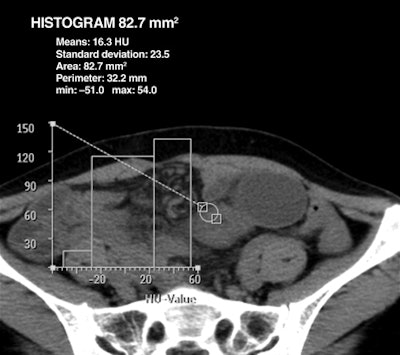

| Woman, 39 years old, with small-bowel obstruction secondary to adhesion. Axial contrast-enhanced (above) and unenhanced (below) CT images through lower abdomen show thickened small bowel with preserved bowel wall enhancement and perilesional mesenteric haziness. Maximal attenuation of ROI on contrast-enhanced CT image above is 114 HU, and subtraction value of maximal attenuation of ROI between contrast-enhanced (above) and unenhanced (below) images is 60 HU at thickened bowel lesion. At surgery, peristalsis and arterial pulsation of bowel were preserved, and there was no bowel lesion of discoloration. Images republished with permission of the American Roentgen Ray Society. |